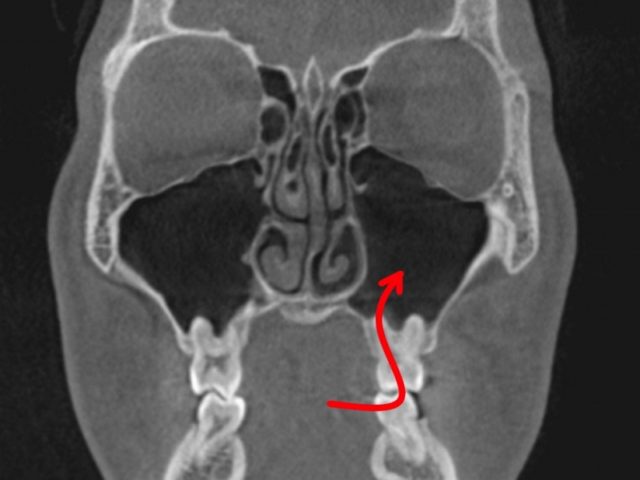

歯性上顎洞炎になりやすい人

上は、上顎洞内に、

大臼歯の歯根が

飛び出しています。

もし、この根が化膿すると、

上顎洞に炎症が波及しやすいでしょう。

この様な方は、

歯性上顎洞炎になりやすいと思われます。